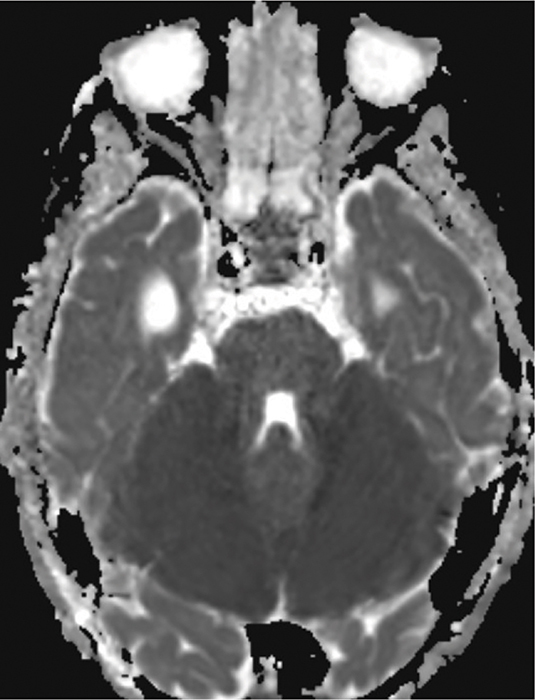

We report the case of a 4‑year‑old child who experienced rapid neurological decline following opioid administration during anesthesia for an interventional procedure to treat a vein of Galen aneurysm. Cerebral magnetic resonance imaging (MRI) revealed marked cytotoxic edema in both cerebellar hemispheres and the brainstem, indicative of opioid‑induced neurotoxicity. A follow‑up MRI, performed 2 weeks later, showed profound cerebellar and brainstem atrophy and showed reduction in mass effect due to cytotoxic edema. Teaching point: Pediatric opioid‑use‑associated neurotoxicity with cerebellar edema (POUNCE) syndrome is a rare condition, characterized by cerebellar edema as a hallmark feature, which can be identified on MRI in pediatric patients following opioid use.

Abstract Image